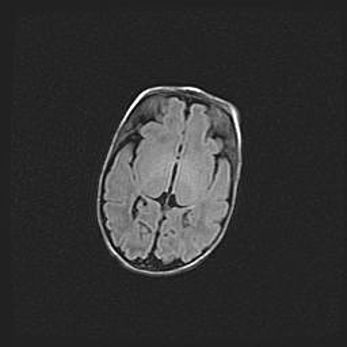

Открытая гидроцефалия.

Возраст: 9 месяцев 12 дней

Вес: 6800 г

Пол: мужской

Окружность головы: 41,5 см

Срок гестации: 28 недель

Гидроцефалия головного мозга у новорожденных имеет характерный признак: опережающий рост окружности головы приводит к визуально хорошо определяемой гидроцефальной форме сильно увеличенного в объёме черепа. Детские неврологи определяют следующие симптомы гидроцефалии у грудничков: выбухающий напряжённый родничок, частое запрокидывание головы, смещение глазных яблок к низу.